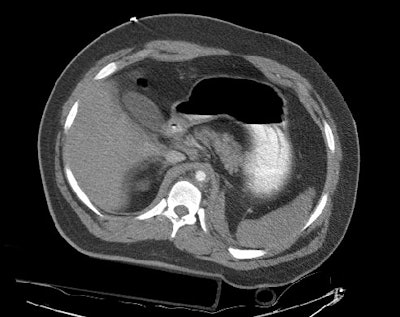

Images through the abdomen revealed a severely diminished aortic caliber and poor organ perfusion consistent with hypovolemic shock. The patient expired prior to angiography.